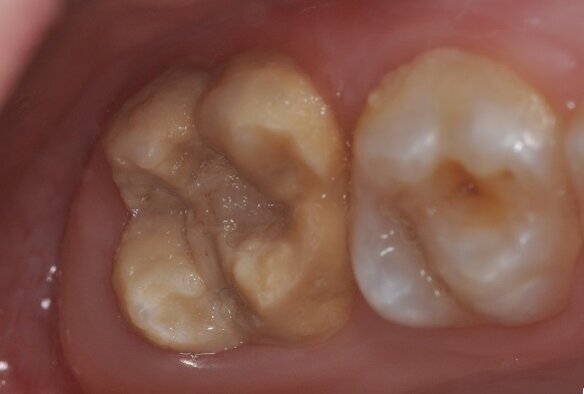

The photograph shows a severe form of MIH. The tooth on the left erupted incompletely developed. The molar was highly sensitive to cold and touch, and brushing was painful, as evident from the surface deposits. The second molar was also affected by the condition. (Photograph: Prof. Norbert Krämer)

With MIH, permanent anterior teeth and, increasingly, second primary molars often present with defective structures. Clinically, the severity may vary greatly, from a single cusp to the entire surface of the tooth. The mild form of MIH appears as white-yellowish or yellow-brown irregular opacities of the occlusal surface or cusps. The severe form exhibits chipped or abraded enamel and dentine of varying degrees. The affected patients suffer from pain when drinking, eating and brushing their teeth.